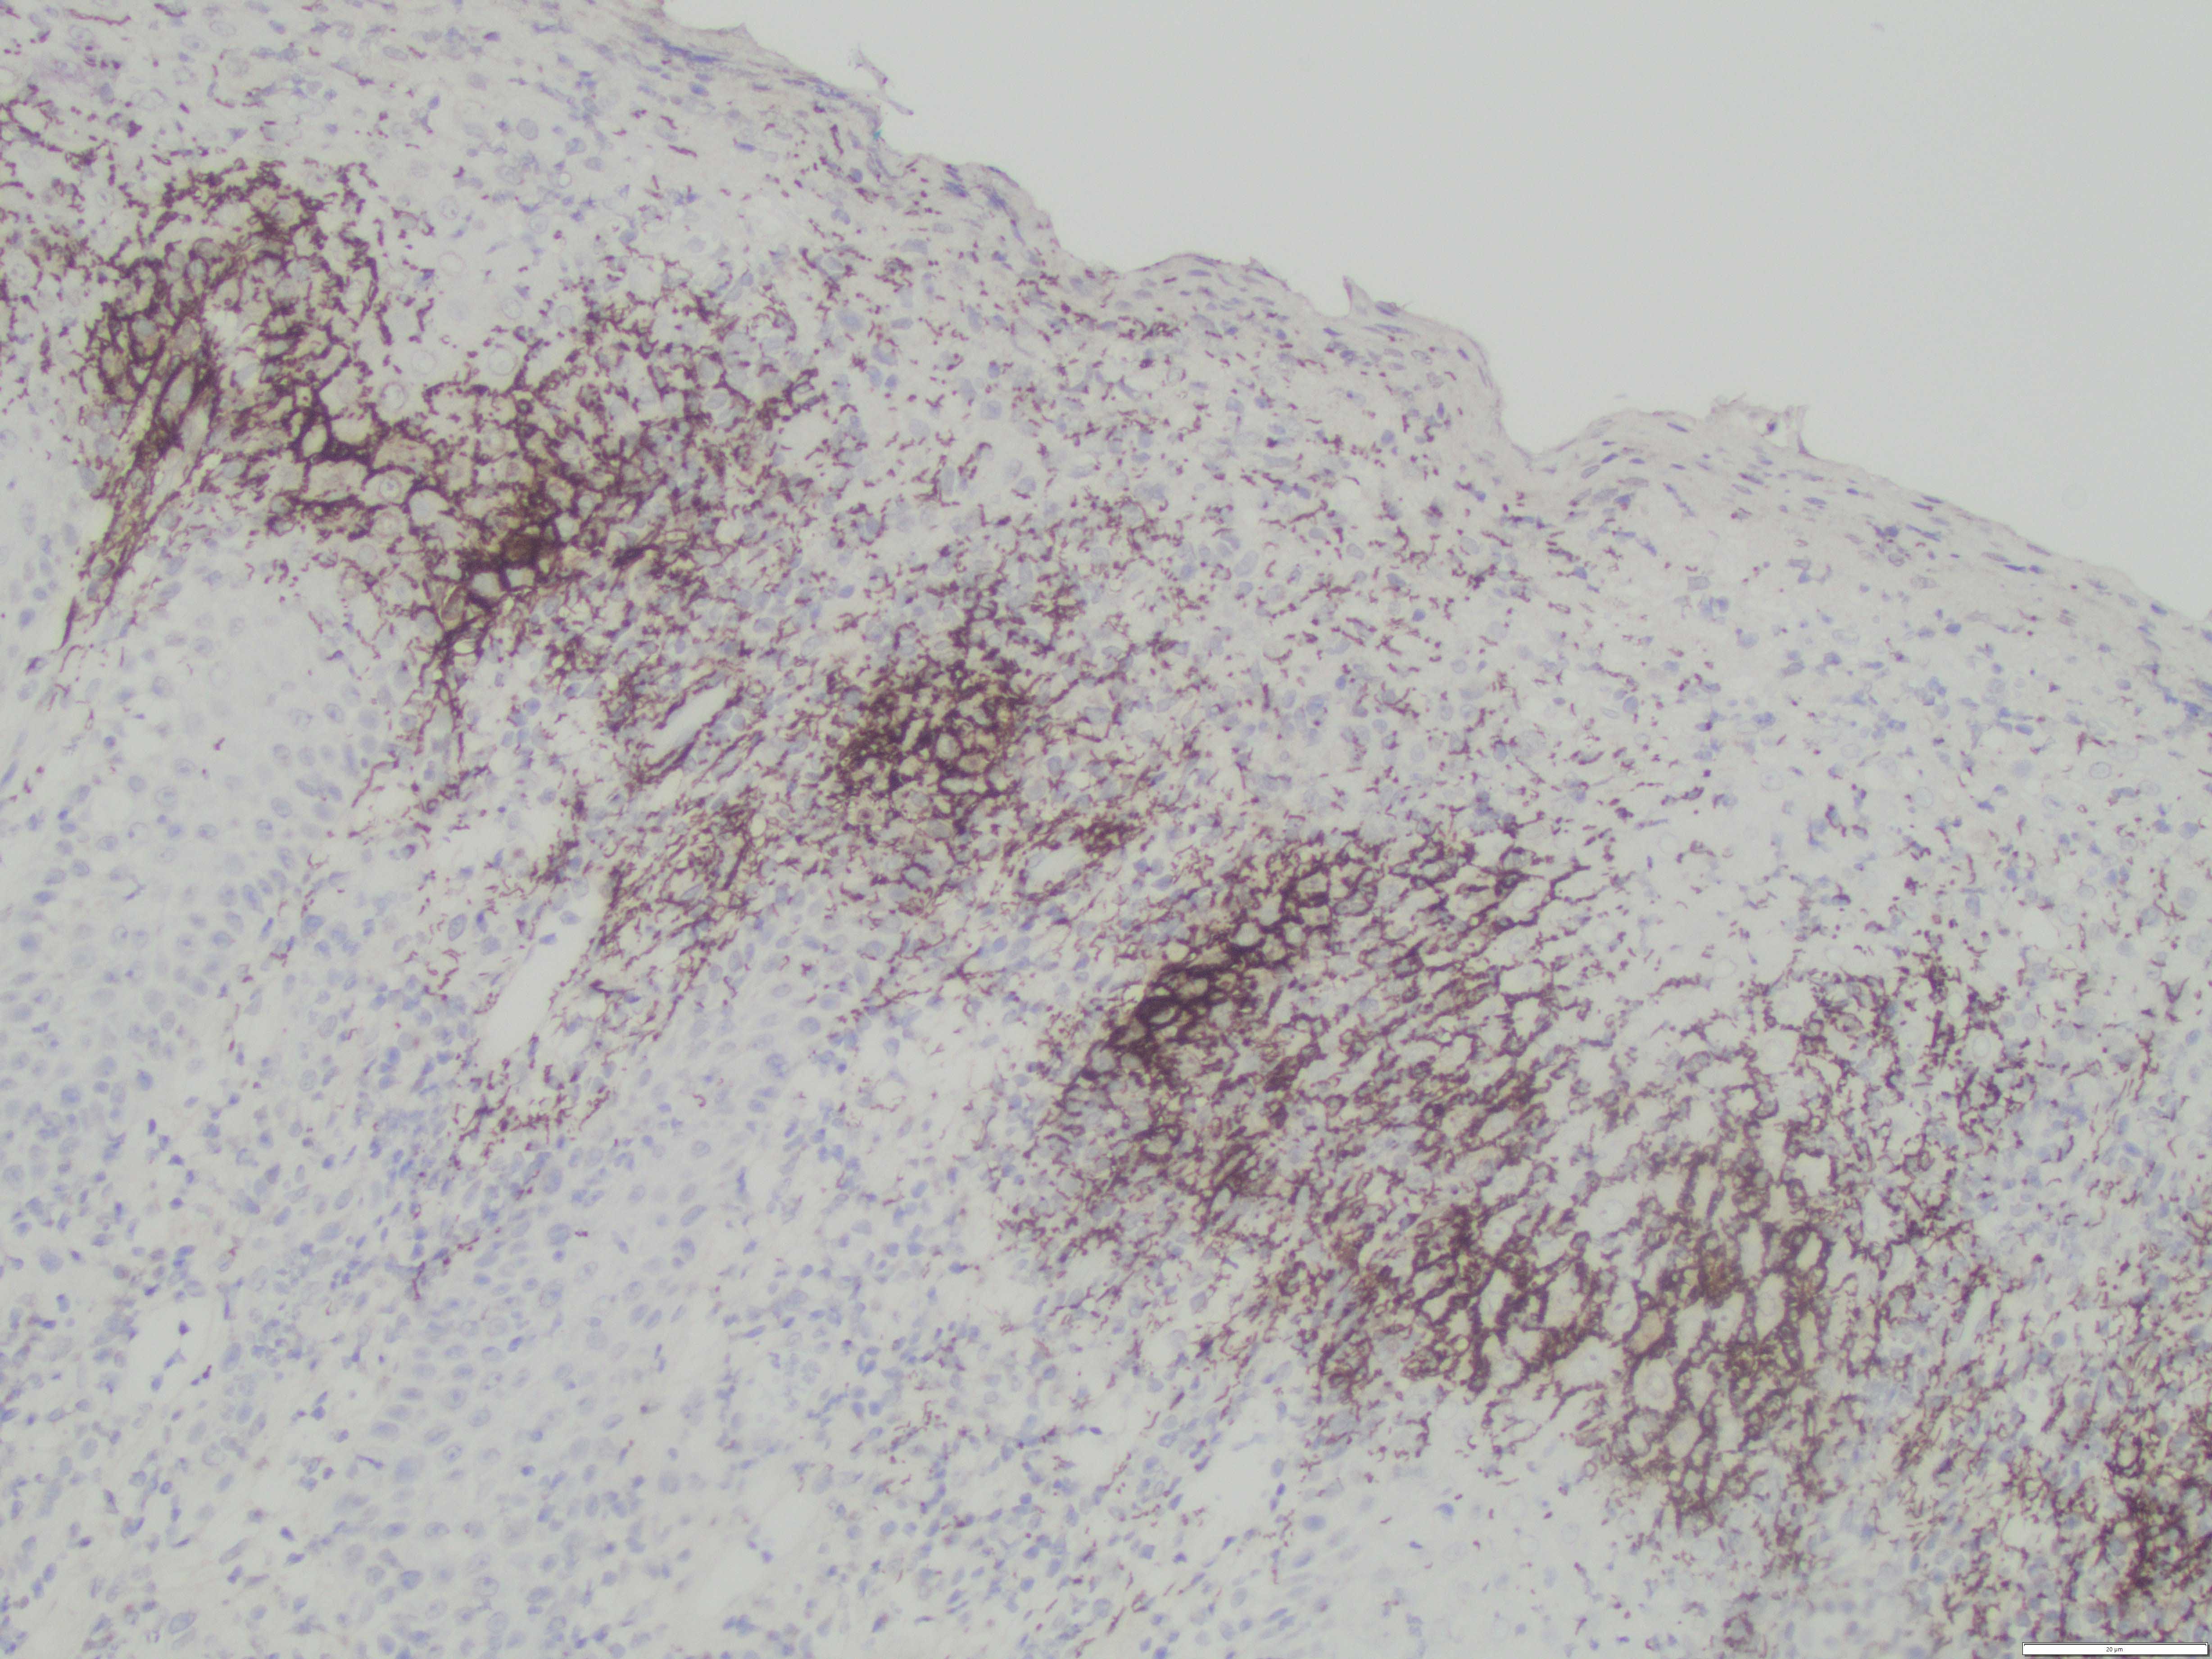

Often, there is high-clinical suspicion for secondary syphilis as these can be highly contagious and contain large number of spirochete organisms, as evidenced by thespirochete immunohistochemical stain.